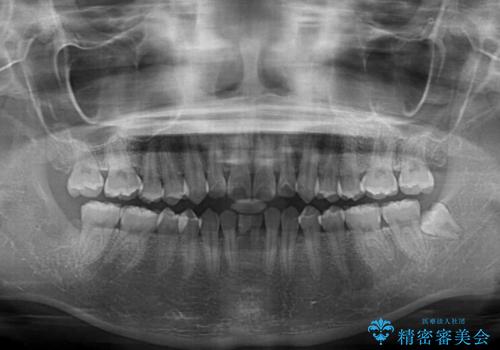

- 下顎前歯に乳歯が残っており、欠損もしていることを気にして来院された患者様です。

舌の突出癖が顕著にあり、上下前歯が非接触となっており、上顎前歯が前方に突出している状態でした。

ワイヤー装置により矯正治療を行うとともに舌突出癖改善のためのトレーニングをしっかりと行っていただき、咬み合わせが安定した位置となったタイミングで下顎前歯にブリッジの仮歯を装着していく計画としました。

結婚式の予定があるとのことで、できる限り歯列を整え、挙式直前で残った乳歯を抜歯してブリッジの仮歯を装着するプランを立てたのですが、途中妊娠をされたため、麻酔をするタイミングを検討し、うまく前歯を整えることができました。